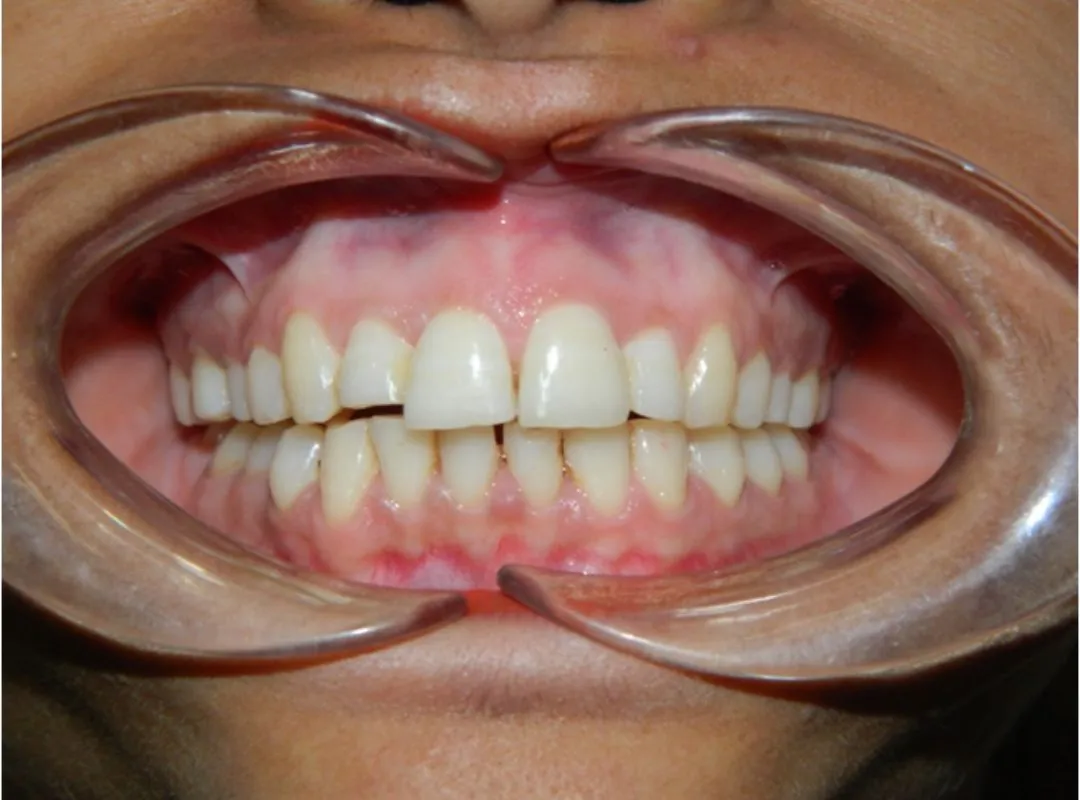

I had undergone my teeth Aligner process at JP dental, Perambur,which was over a period of 8 months. Journey was of 12 levels of aligners and after each level my teeth were thoroughly evaluated to ensure the process was smooth and progressive. The doctors here are very professional and have upto date equipments which gave me a very great outcome from my journey here. Highly recommend .create a caption for this review